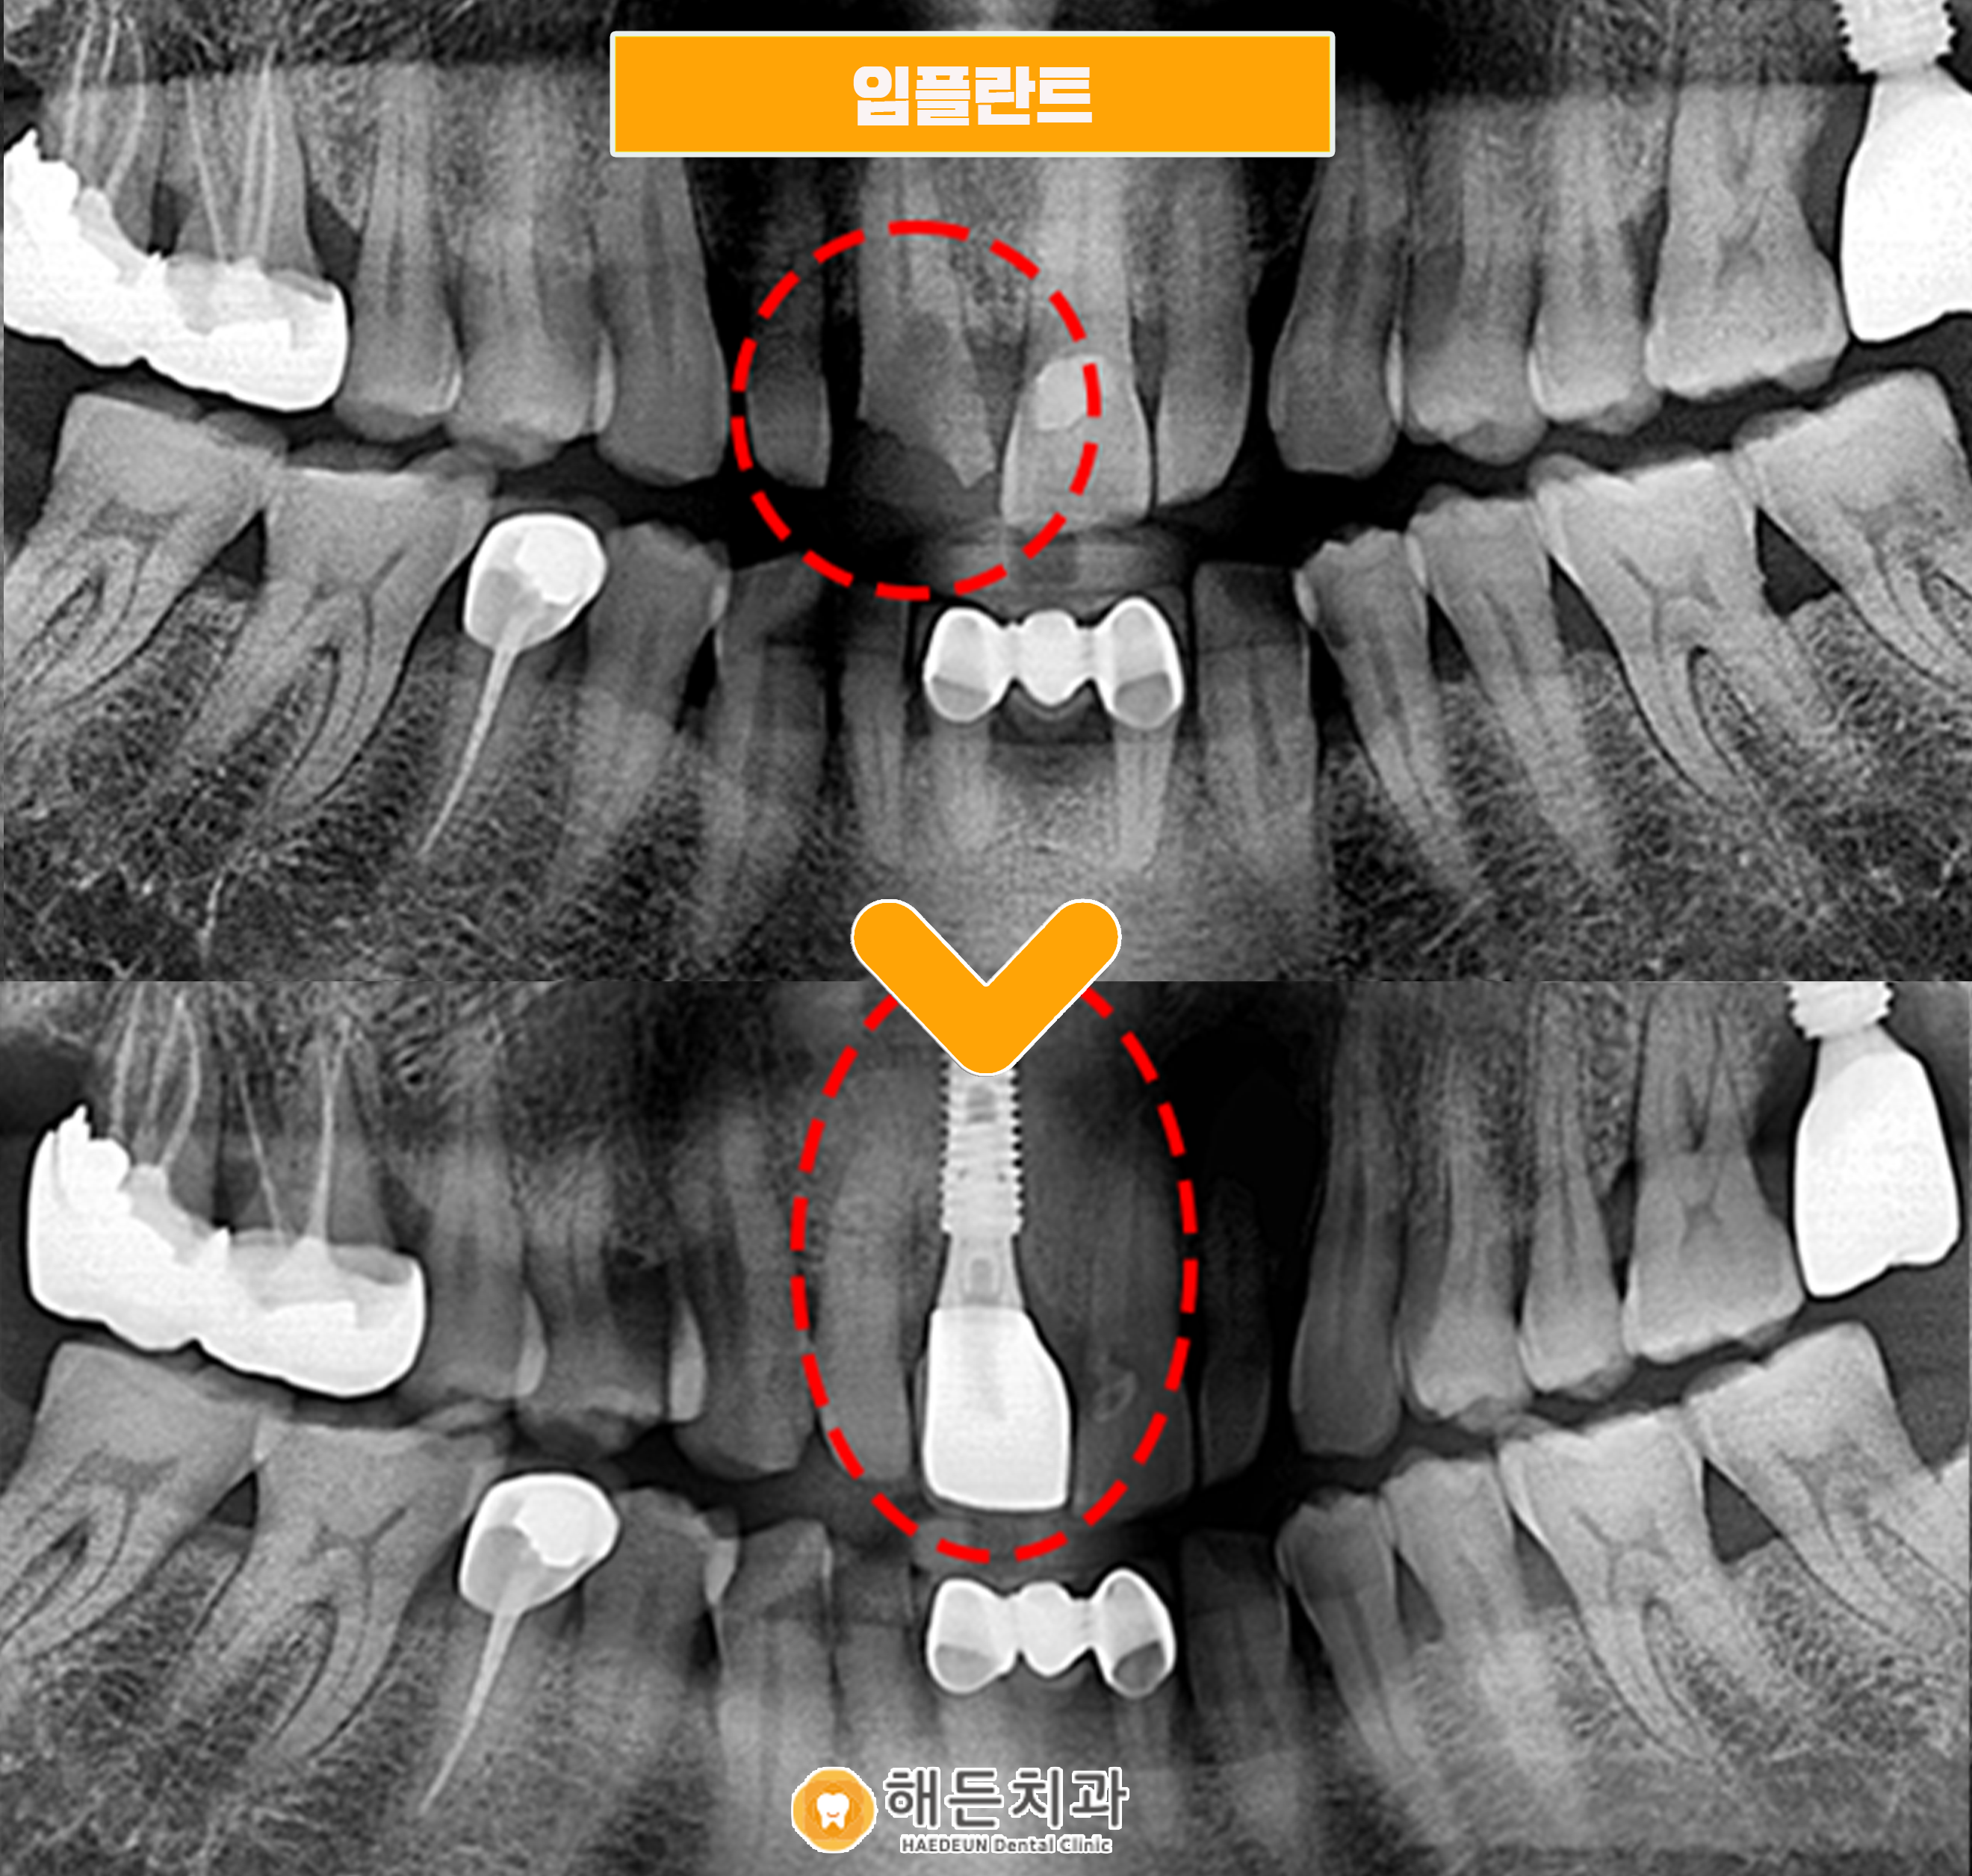

치아 신경까지 파절이 되어 자연치아가 더 이상 잇몸에 고정되지 못하고 흔들리는 현상까지 나타났습니다.

신경치료를 진행하기에는 치아 신경 파절과 흔들림이 너무 심하여 임플란트를 진행하게 되었습니다.

임플란트를 진행하기 전 정밀한 해부학적 분석이 가능한 CT 장비인 3D-CT 촬영을 통해

환자분의 임플란트 식립을 위한 체계적인 계획과 상담을 먼저 진행하였습니다.

먼저 발치를 하고, 임플란트 식립을 진행하였습니다.